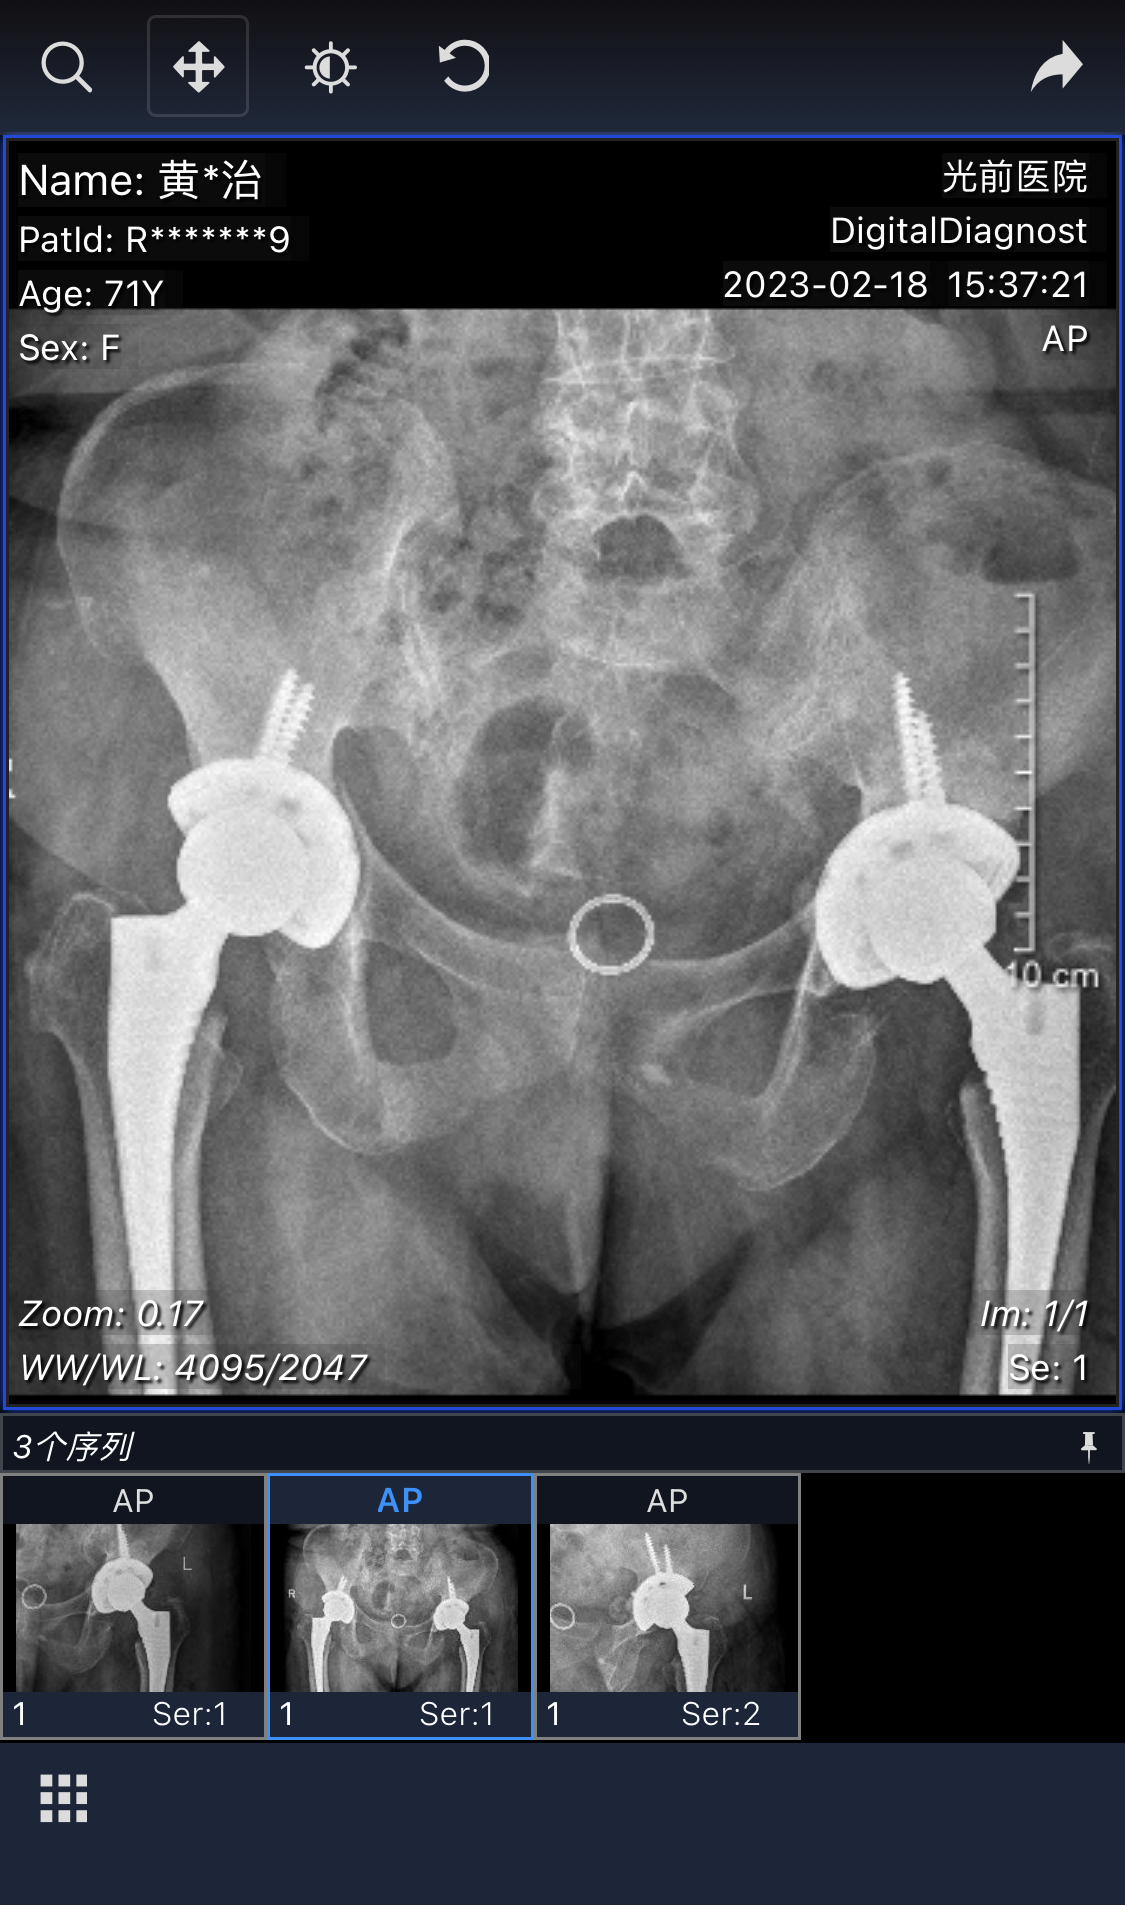

今年2月13日,黃阿婆再次入院行左側(cè)髖關(guān)節(jié)置換(因疫情而推遲)。術(shù)前檢查發(fā)現(xiàn),左側(cè)髖關(guān)節(jié)股骨頭壞死程度較右側(cè)更嚴(yán)重,股骨頭已缺損,髖臼骨溶解厲害,骨贅增生嚴(yán)重,黃主任及其團(tuán)隊(duì)經(jīng)過充分的術(shù)前討論、手術(shù)設(shè)計(jì),為黃阿婆順利完成了左側(cè)髖關(guān)節(jié)置換。術(shù)后第2天,黃阿婆即可站起來;第3天扶助行器開始下地站立;5天后,已能自己扶著助行器在病房走廊行走自如,且沒有明顯痛感,生活能自理,擺脫以往方便時(shí)需要靠人攙扶的窘境。

手術(shù)前后對(duì)比

2月23日,黃阿婆康復(fù)出院,陳阿公對(duì)骨科醫(yī)護(hù)團(tuán)隊(duì)的精心診治與暖心護(hù)理十分感激,感慨骨科“是真功夫技術(shù)精湛,最用心妙手回春”,再次揮筆寫下一首詩(shī)以表感激之情。他開心地告訴醫(yī)護(hù)人員:“現(xiàn)在老伴能下地走路了,我倆也上了年紀(jì),沒辦法再干農(nóng)活了,以后也可以一起出去走走散散心了?!?/span>